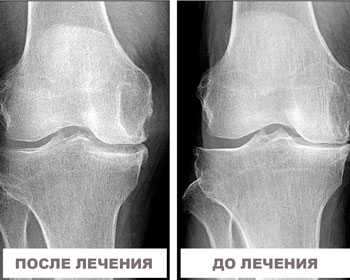

Результаты наших пациентов ДО и ПОСЛЕ лечения

Артроз колена 3 стадии, отправляли на операцию по замене сустава. При помощи плазмы за 3 сеанса справилась с артрозом. Отказалось от трости. Избежала операции. Болей нет, восстановлен хрящ и сумка сустава. Срок лечения - неделя.